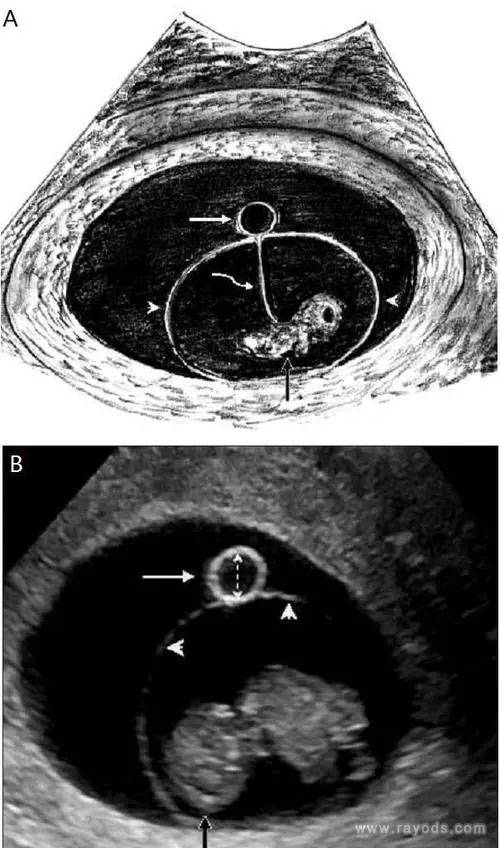

当孕囊平均直径在5-6mm时,通过阴道超声就可发现卵黄囊,正常来说,卵黄囊中央无回声,周边厚薄一致,边界清晰的环形高回声,具体如下图:

A.图白色箭头显示妊娠囊内的正常卵黄囊,黑色箭头表示胚胎,在其中还可见羊膜、羊膜囊、绒毛膜囊和卵黄管等组织

B.图为经阴道超声显示妊娠第9周的存活胚胎以及卵黄囊。